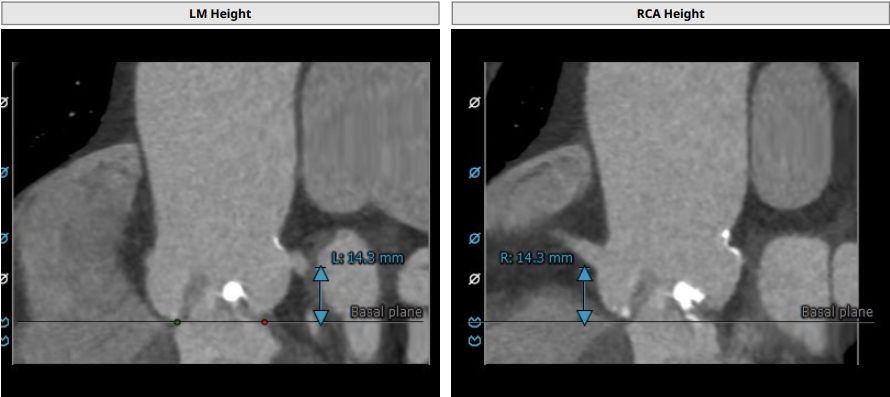

左冠高度:14.3 mm,右冠高度:14.3 mm

患者为TYPE0型二叶瓣,重度钙化,钙化主要分布在左侧瓣叶,瓣叶前后交界缘均可见局部融合,瓣环平面可见钙化,并延伸至左室流出道,左右冠开口高度均为14.3 mm,法式窦结构可,无明显冠脉阻塞风险。心脏角度约38°,左室不大,心肌肥厚,升主动脉可见增宽。